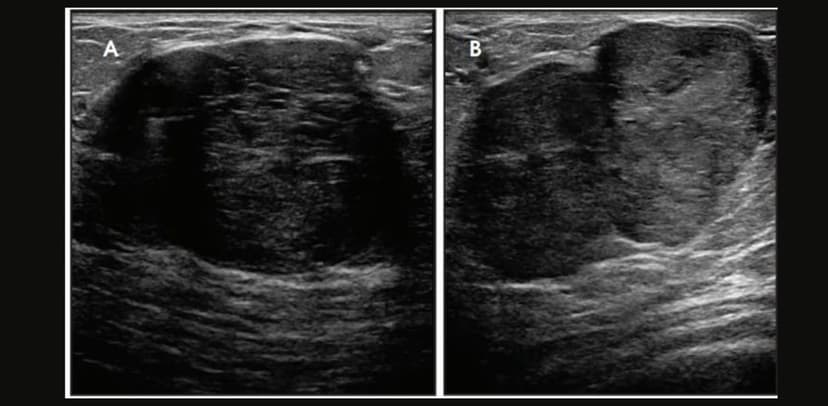

Nhân giảm âm tuyến vú là tổn thương dạng khối, thường ở thể đặc, tồn tại trong tuyến vú. Hầu hết người bệnh mắc nhân giảm âm đều được phát hiện tình cờ qua kiểm tra sức khỏe định kỳ có thực hiện chẩn đoán hình ảnh vú như x-quang hay siêu âm…

Hình ảnh nhân giảm âm tuyến vú được phát hiện qua siêu âm tại Thu Cúc TCI.